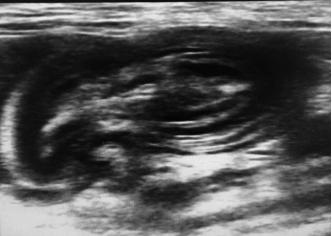

d.超声检查。消化道超声部分属于其他范畴,此处不做赘述。能够识别肠套叠即可。

肠套叠,可见肠道内容物有肠道分层结构